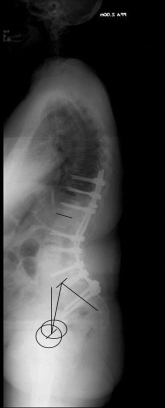

X-ray image before and after surgery. The patient underwent spinal surgery at another hospital and increasingly developed other complaints. The X-ray showed a complete loss of the hollow back and a resulting change in balance. A so-called lordosis operation led to a restoration of a normal hollow back and thus a normal spinal balance and finally to regressive complaints.